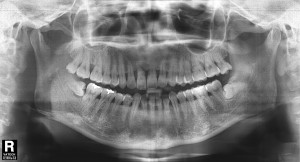

김정아 앞니 치료전

앞니 임플란트 치료를 하고 싶어서 내원하신 환자분입니다.

오래 전에 앞니를 부딪혀서 금이 갔었는데 따로 치료를 받지 않으시고 약 5년간 방치하신 상태였습니다.